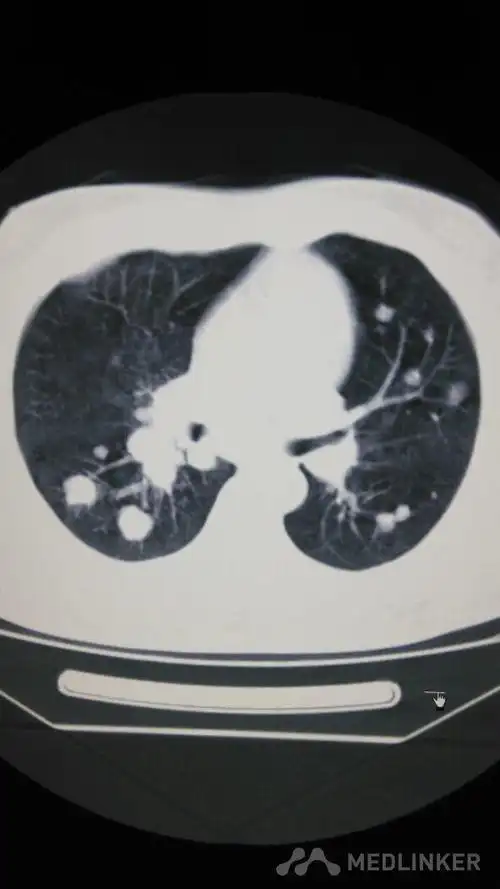

中央型肺癌ct

简述中央型肺癌特点及影像表现

中央型肺癌一例直接征象和间接征象都有哪些